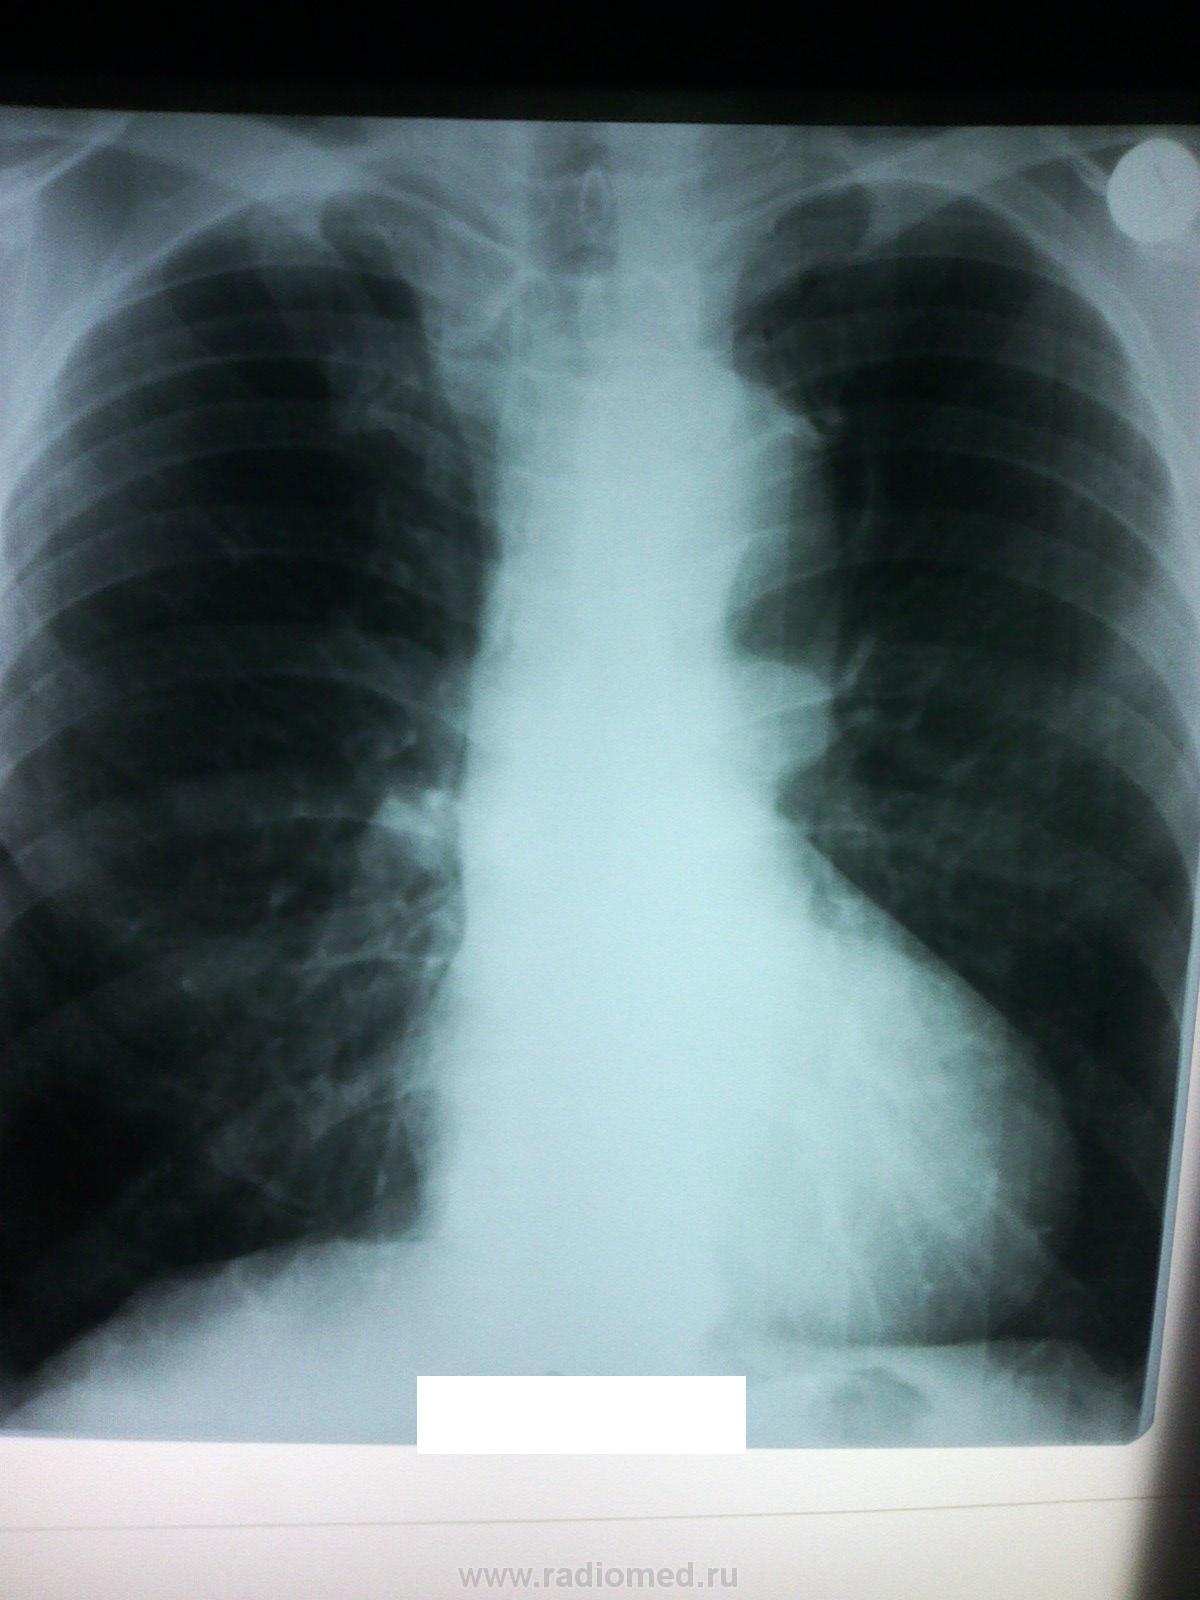

Пациент, 62 года, DS:ХОБЛ. Есть только заключение КТ и распечатка на листке бумаги. Архива нет. Тревожит корень слева. Хотелось бы узнать вашего мнения. P.S> Обработать изображения не имею возможностей (

Не похоже на объемную патологию, а на легочную гипертензию?

Моё впечатление - сосуд. Тоже непонятно про КТ... Может, как норму расценили.

Спасибо! Вот и мое впечатление, что сосуд, но что за сосуд? Аорта на этих жалостливых распечатках ровная, четкая. Сам пациент никаких жалоб не предъявляет, ничего не тревожит. Была мысль за аномалию какую-либо...

В протоколе указано: "Крупные сосуды не расширены"